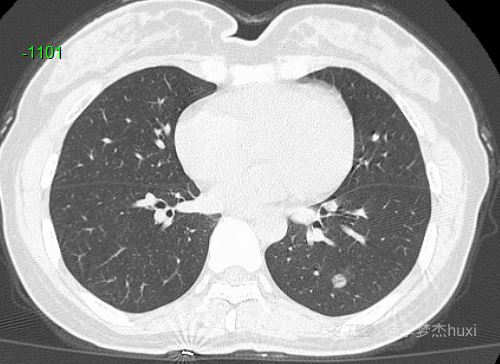

病例女性45岁,体检发现PET-CT阴性的肺结节,猜病理。

患者性别:女

患者年龄:45岁

主诉:体检发现肺结节,PET-CT阴性。